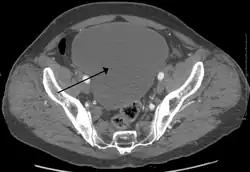

| Urinary retention with greatly enlarged bladder as seen by CT scan. | |

As seen on axial CT